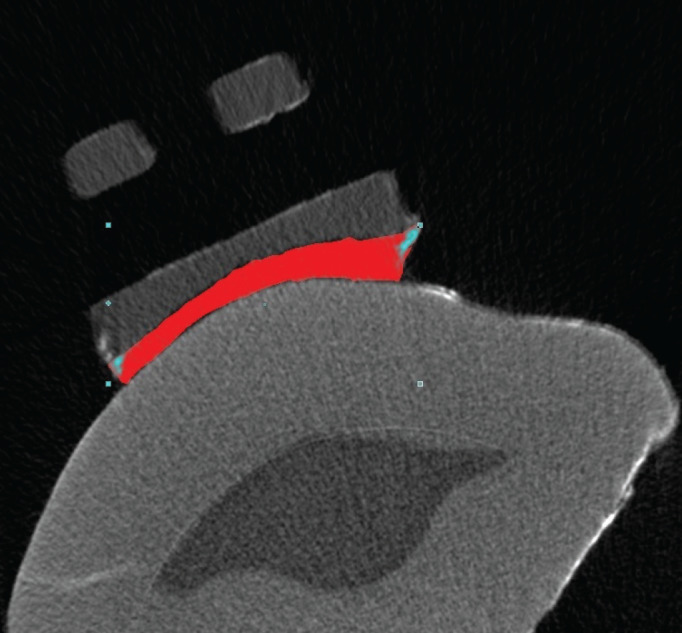

Methods: Forty extracted human maxillary premolar teeth were randomly divided into five groups. According to the groups, adhesive coated and conventional bracket systems were bonded to the tooth surfaces with the specified adhesive agents. To simulate a six-month oral environment, all teeth were subjected to a thermal cycle procedure. Micro-computed tomography (micro-CT) was used to view and measure the microleakage. Kruskal-Wallis test was used to compare the parameters and Mann-Whitney U test was used for the determination of the group that caused the difference. For intragroup comparisons Wilcoxon signed-rank test was used.

Results: Microleakage volume (mm3) and microleakage percentage (%) measured in Blugloo™ group was found significantly lower (p<0.05) then other groups. There was no significant difference in microleakage volume (mm3) and percentage (%) in comparison of gingival and occlusal regions (p>0.05).

Conclusion: Adhesive precoated flash-free brackets were not shown a significant difference compared to their conventional equivalent for microleakage volume. The brackets bonded with Blugloo™ adhesive were showed significant less microleakage than the other groups.